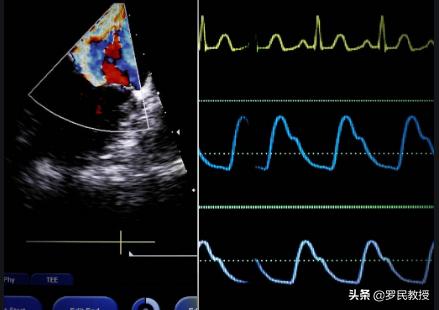

2, l'échographie cardiaque est cruciale dans l'examen des maladies cardiaques, mais tous les patients n'en ont pas besoin, elle se concentre principalement sur la structure et la fonction du cœur, tant que le patient n'est pas atteint d'une cardiopathie congénitale, d'une cardiomyopathie dilatée, d'une insuffisance cardiaque et d'autres problèmes, les résultats de l'examen sont normaux, ce qui n'est pas inhabituel.

2. échographie cardiaque

Si l'on compare le cœur à une maison, un ECG vérifie le système électrique de la maison et une première évaluation de l'ouverture des tuyaux, puis une échographie cardiaque vérifie les portes, les fenêtres et les murs. Il n'y a pas de corrélation directe entre une échographie cardiaque et le fait de commettre ou non une maladie. Si l'échographie est normale, on peut exclure une cardiopathie valvulaire, une cardiomyopathie, une hypertrophie du cœur, une insuffisance cardiaque, etc.